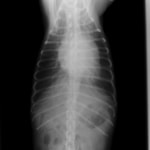

A・B:猫の肥大型心筋症による胸水の貯留 正面像と側面像

C:猫の肥大型心筋症による肺水腫 側面像

D:Cの肺水腫治癒後 側面像